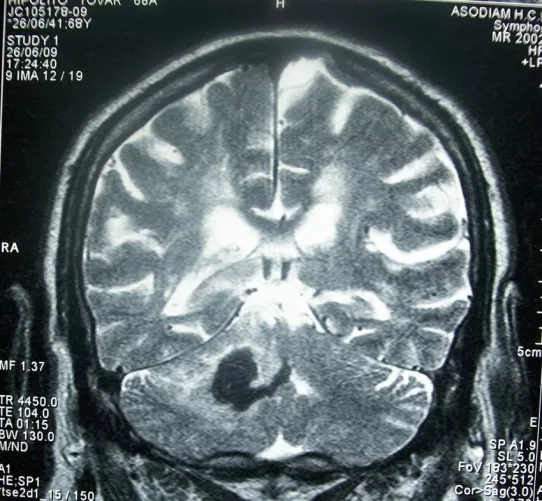

Stroke - Agyvérzés CT-felvételen